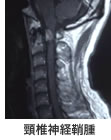

首や腰の症状があった場合、稀に脊髄腫瘍が存在することがあります。脊髄腫瘍の中にも「硬膜外腫瘍」、「硬膜内髄外腫瘍」、「髄内腫瘍」と腫瘍の発生する 場所により分けられ、また腫瘍が「良性」であるか、「悪性」であるか、腫瘍の大きさや周囲の組織への浸潤度により治療方法が異なってきます。